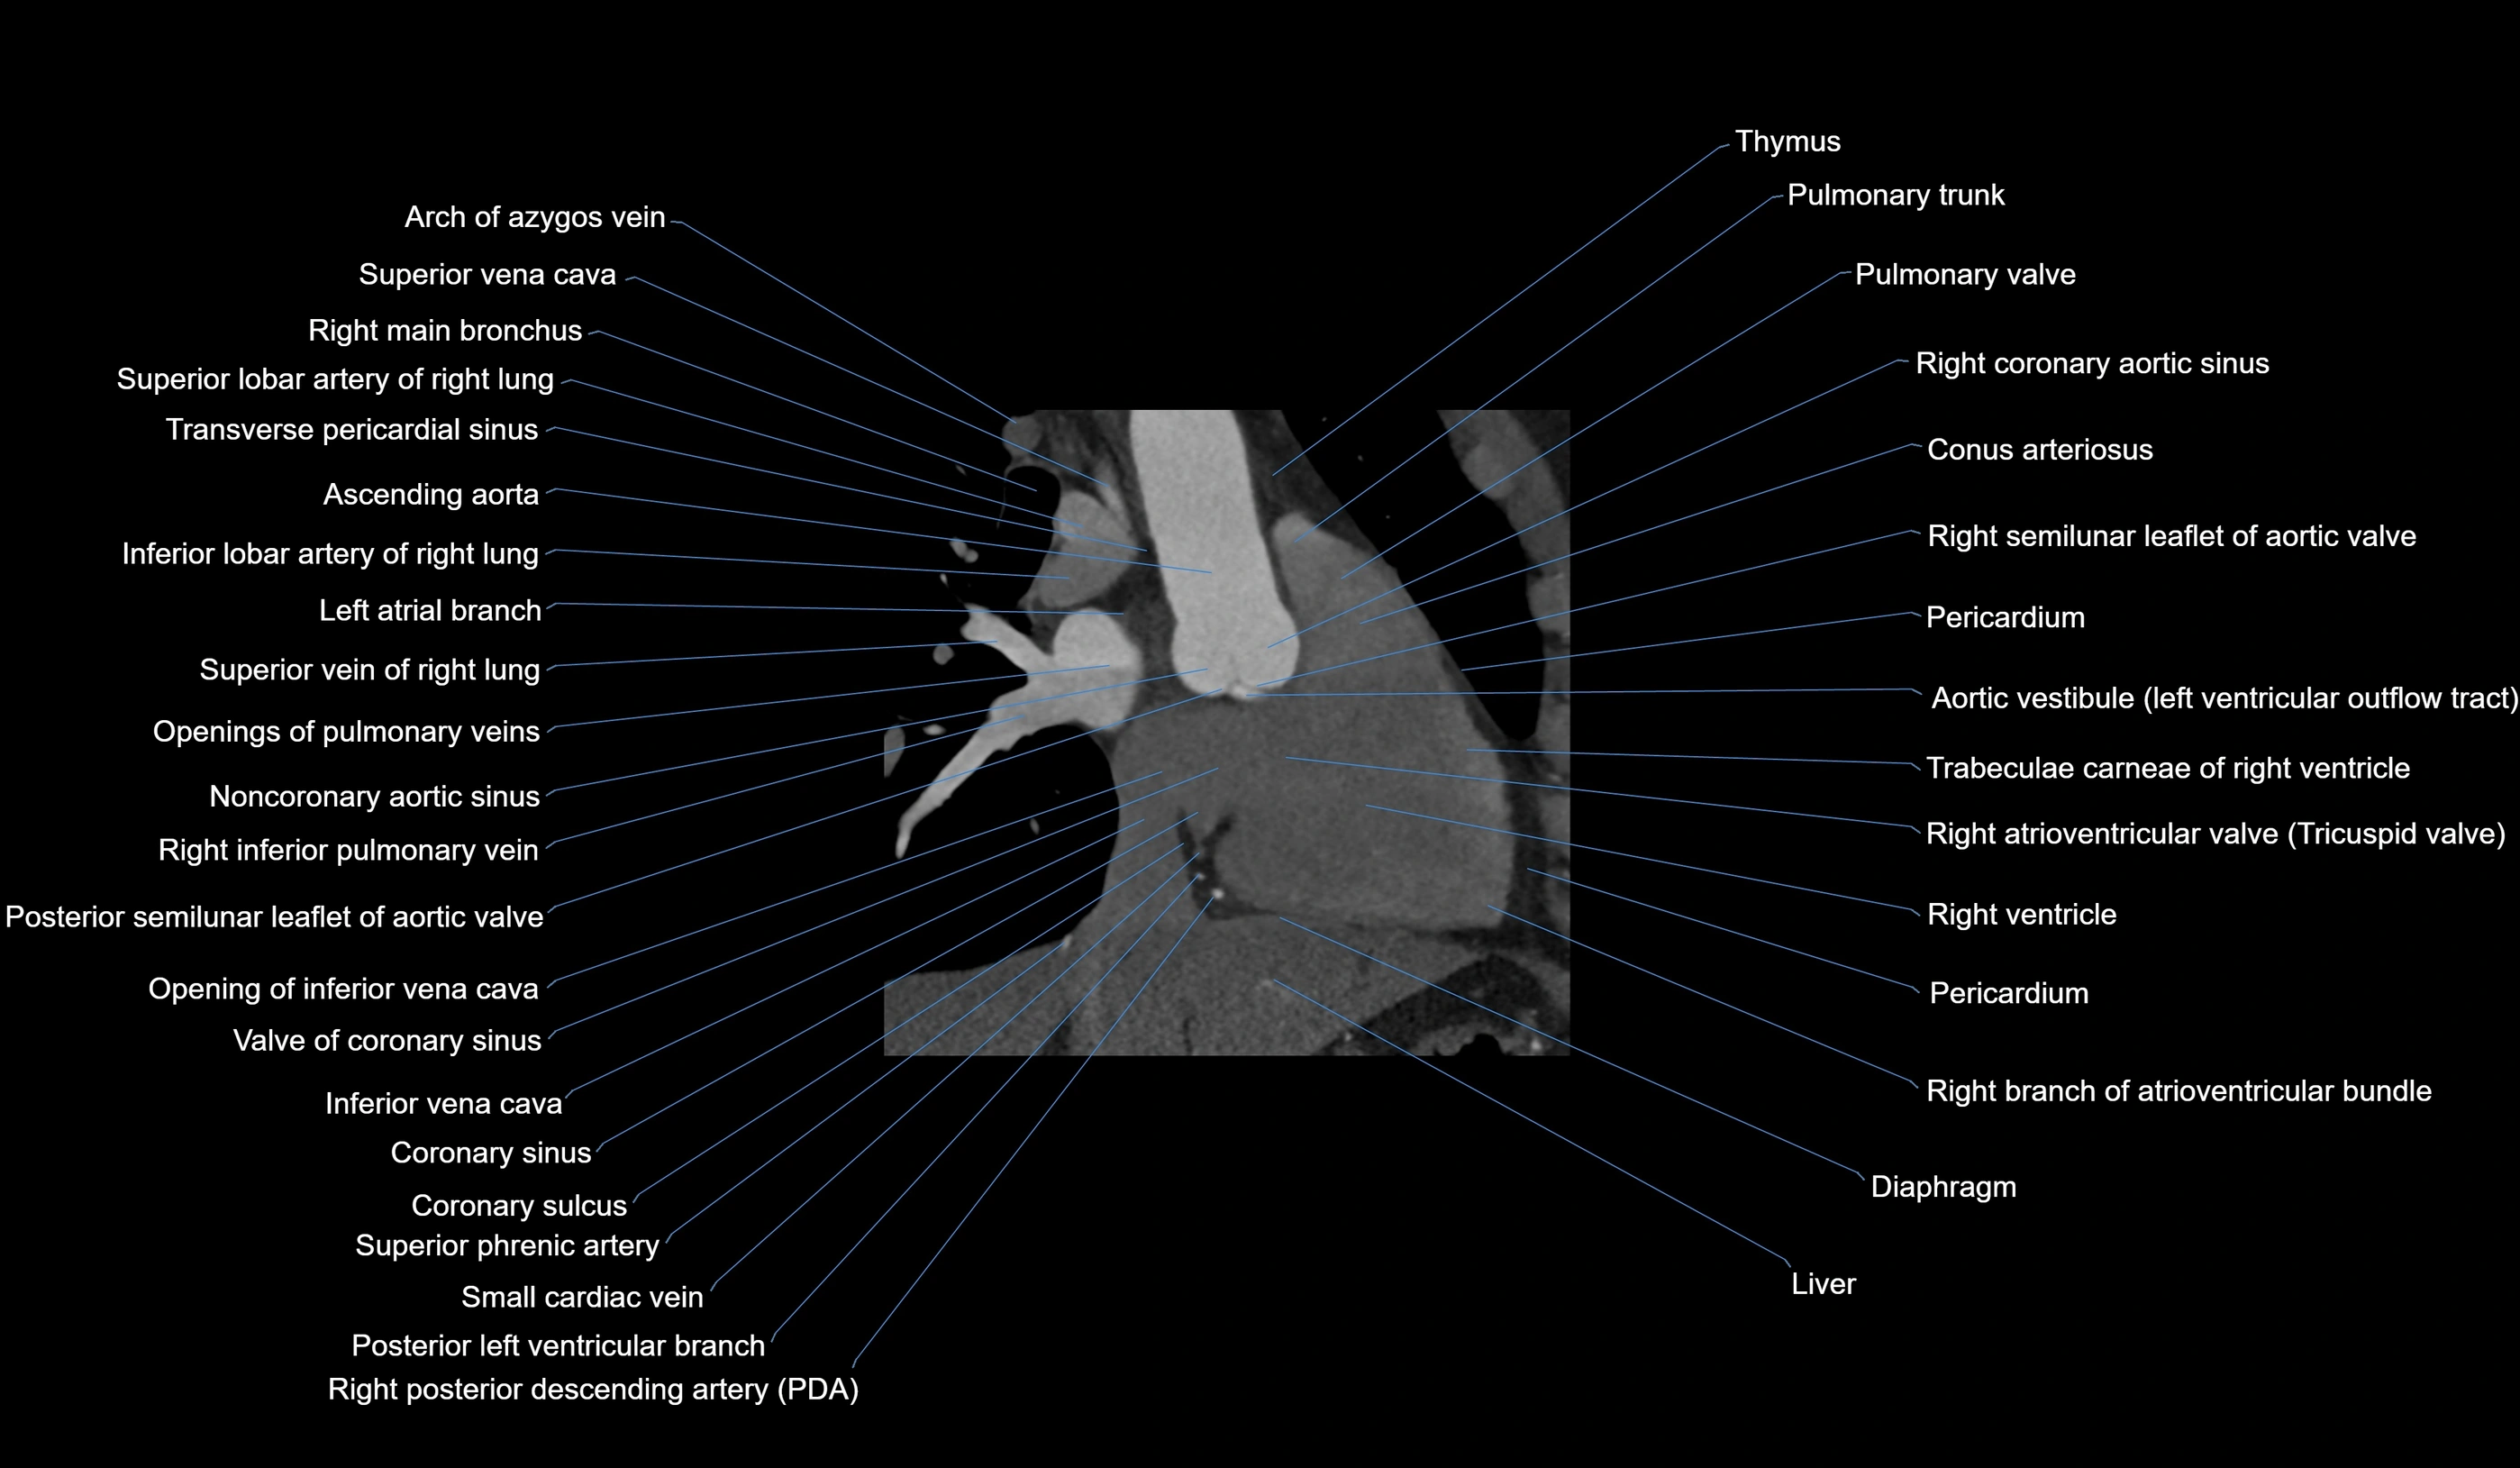

CT images